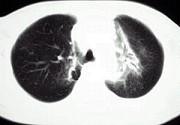

问题 淋巴瘤患者放疗后3个月出现气急咳嗽,CT如图,应考虑为 ( )

选项 A.陈旧性结核 B.放射性肺炎 C.浸润型肺结核 D.瘢痕癌 E.硅沉着病结节

答案 B